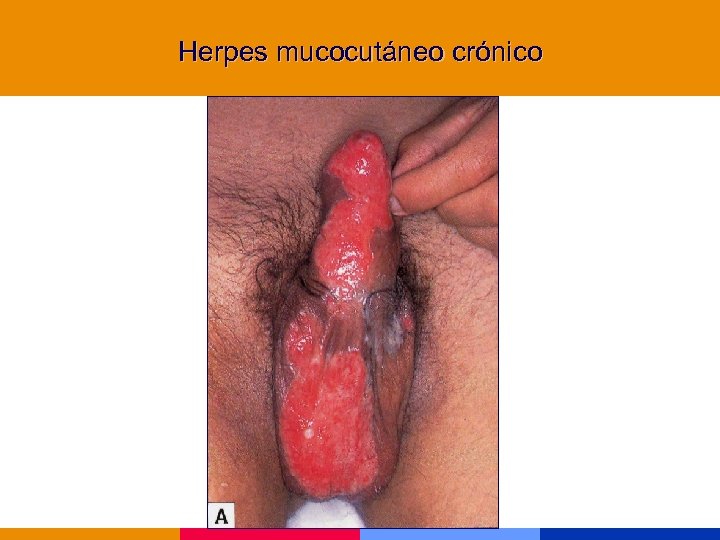

Herpes mucocutáneo crónico

Herpes mucocutáneo crónico

Herpes genital

Herpes genital